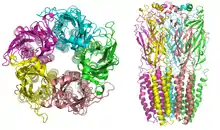

La maladie infectieuse Covid-19 est provoquée par le coronavirus SARS-CoV-2.

Pénétration dans l'organisme et physiopathologie

Les virus infectent généralement les cellules en y entrant via une endocytose médiée par un récepteur auquel chaque virus doit d'abord se lier. Le récepteur utilisé par le SARS-CoV-2 est une protéine de surface cellulaire : l'enzyme de conversion de l'angiotensine 2 (ACE2), la même que pour le SARS-CoV mais avec une affinité 10 à 20 fois plus importante que le SARS-CoV[63]. Le virus se lie avec le récepteur ACE2 par ses protéines présentes dans les épines (spicules) de sa couronne (protein spike)[63].